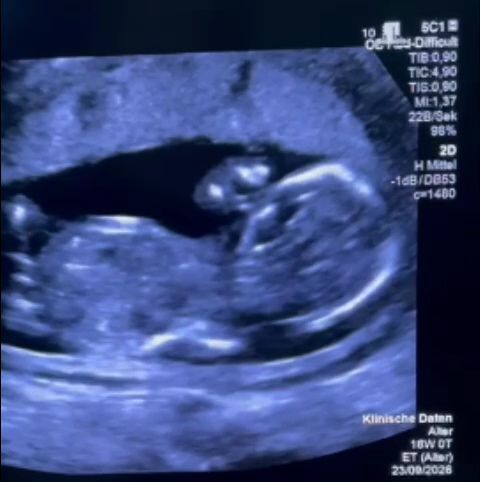

Femeia, aflată în a 12-a săptămână de sarcină, a fost diagnosticată cu o malformație minoră, dar care necesita intervenție medicală rapidă. Părinții au ales să caute ajutor la Spitalul Filantropia din București, unde au avut parte de un tratament descris de Althamer ca fiind degradant. Tatal a fost îndepărtat din spital, iar mamei i s-a cerut să renunțe la telefonul mobil și obiectele personale înainte de consultație.

În timpul consultului, femeia a fost înconjurată de mai multe persoane, iar informațiile despre starea ei au fost interpretate de mai multe persoane. I s-a cerut să efectueze o amniocenteză, o procedură invazivă, înainte de a se interveni pentru corectarea malformației. Femeii însărcinate nu i s-au oferit informații concrete despre medicul care ar fi efectuat procedura, experiența acestuia sau șansele reale de succes.

Familia a solicitat documente pentru a putea beneficia de tratament gratuit în străinătate, dar a fost refuzată. În ciuda insistențelor, femeia nu a primit o scrisoare medicală, ci un raport de cinci rânduri referitor la ecografia efectuată. Din cauza lipsei de alternative, părinții au decis să plece în Germania, unde au fost programați pentru intervenție. Profesorul Thomas Kohl, un specialist german, a subliniat importanța intervenției rapide, afirmând că nu mai era timp de pierdut.